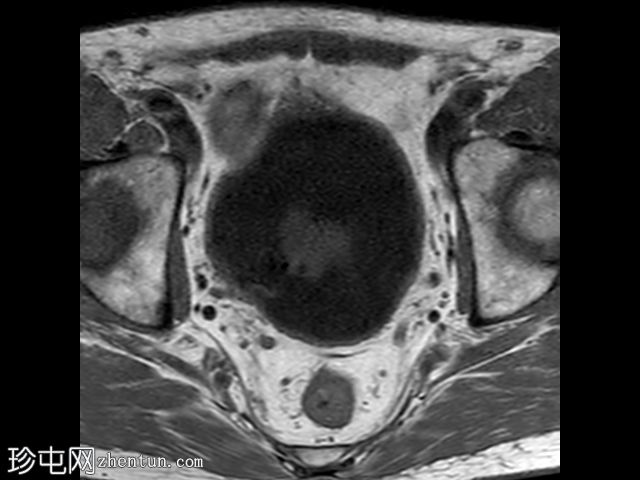

在T1和T2加权像上,于膀胱底部及右下外侧面偶然发现一处呈蛇形缠绕状的低信号区。动态序列中可见快速对比增强,提示所有影像学表现均源于血管,信号缺失与动静脉畸形有关,该畸形至少由膀胱下动脉供血,并由同侧局部扩张的静脉回流。

这些影像学表现符合局限性动静脉畸形,这种情况极为罕见。通常情况下,该畸形伴有肉眼血尿,但本例患者未出现此症状。通常情况下,该畸形由髂内动脉的多条供血动脉供血,血管造影被认为是确诊的金标准。